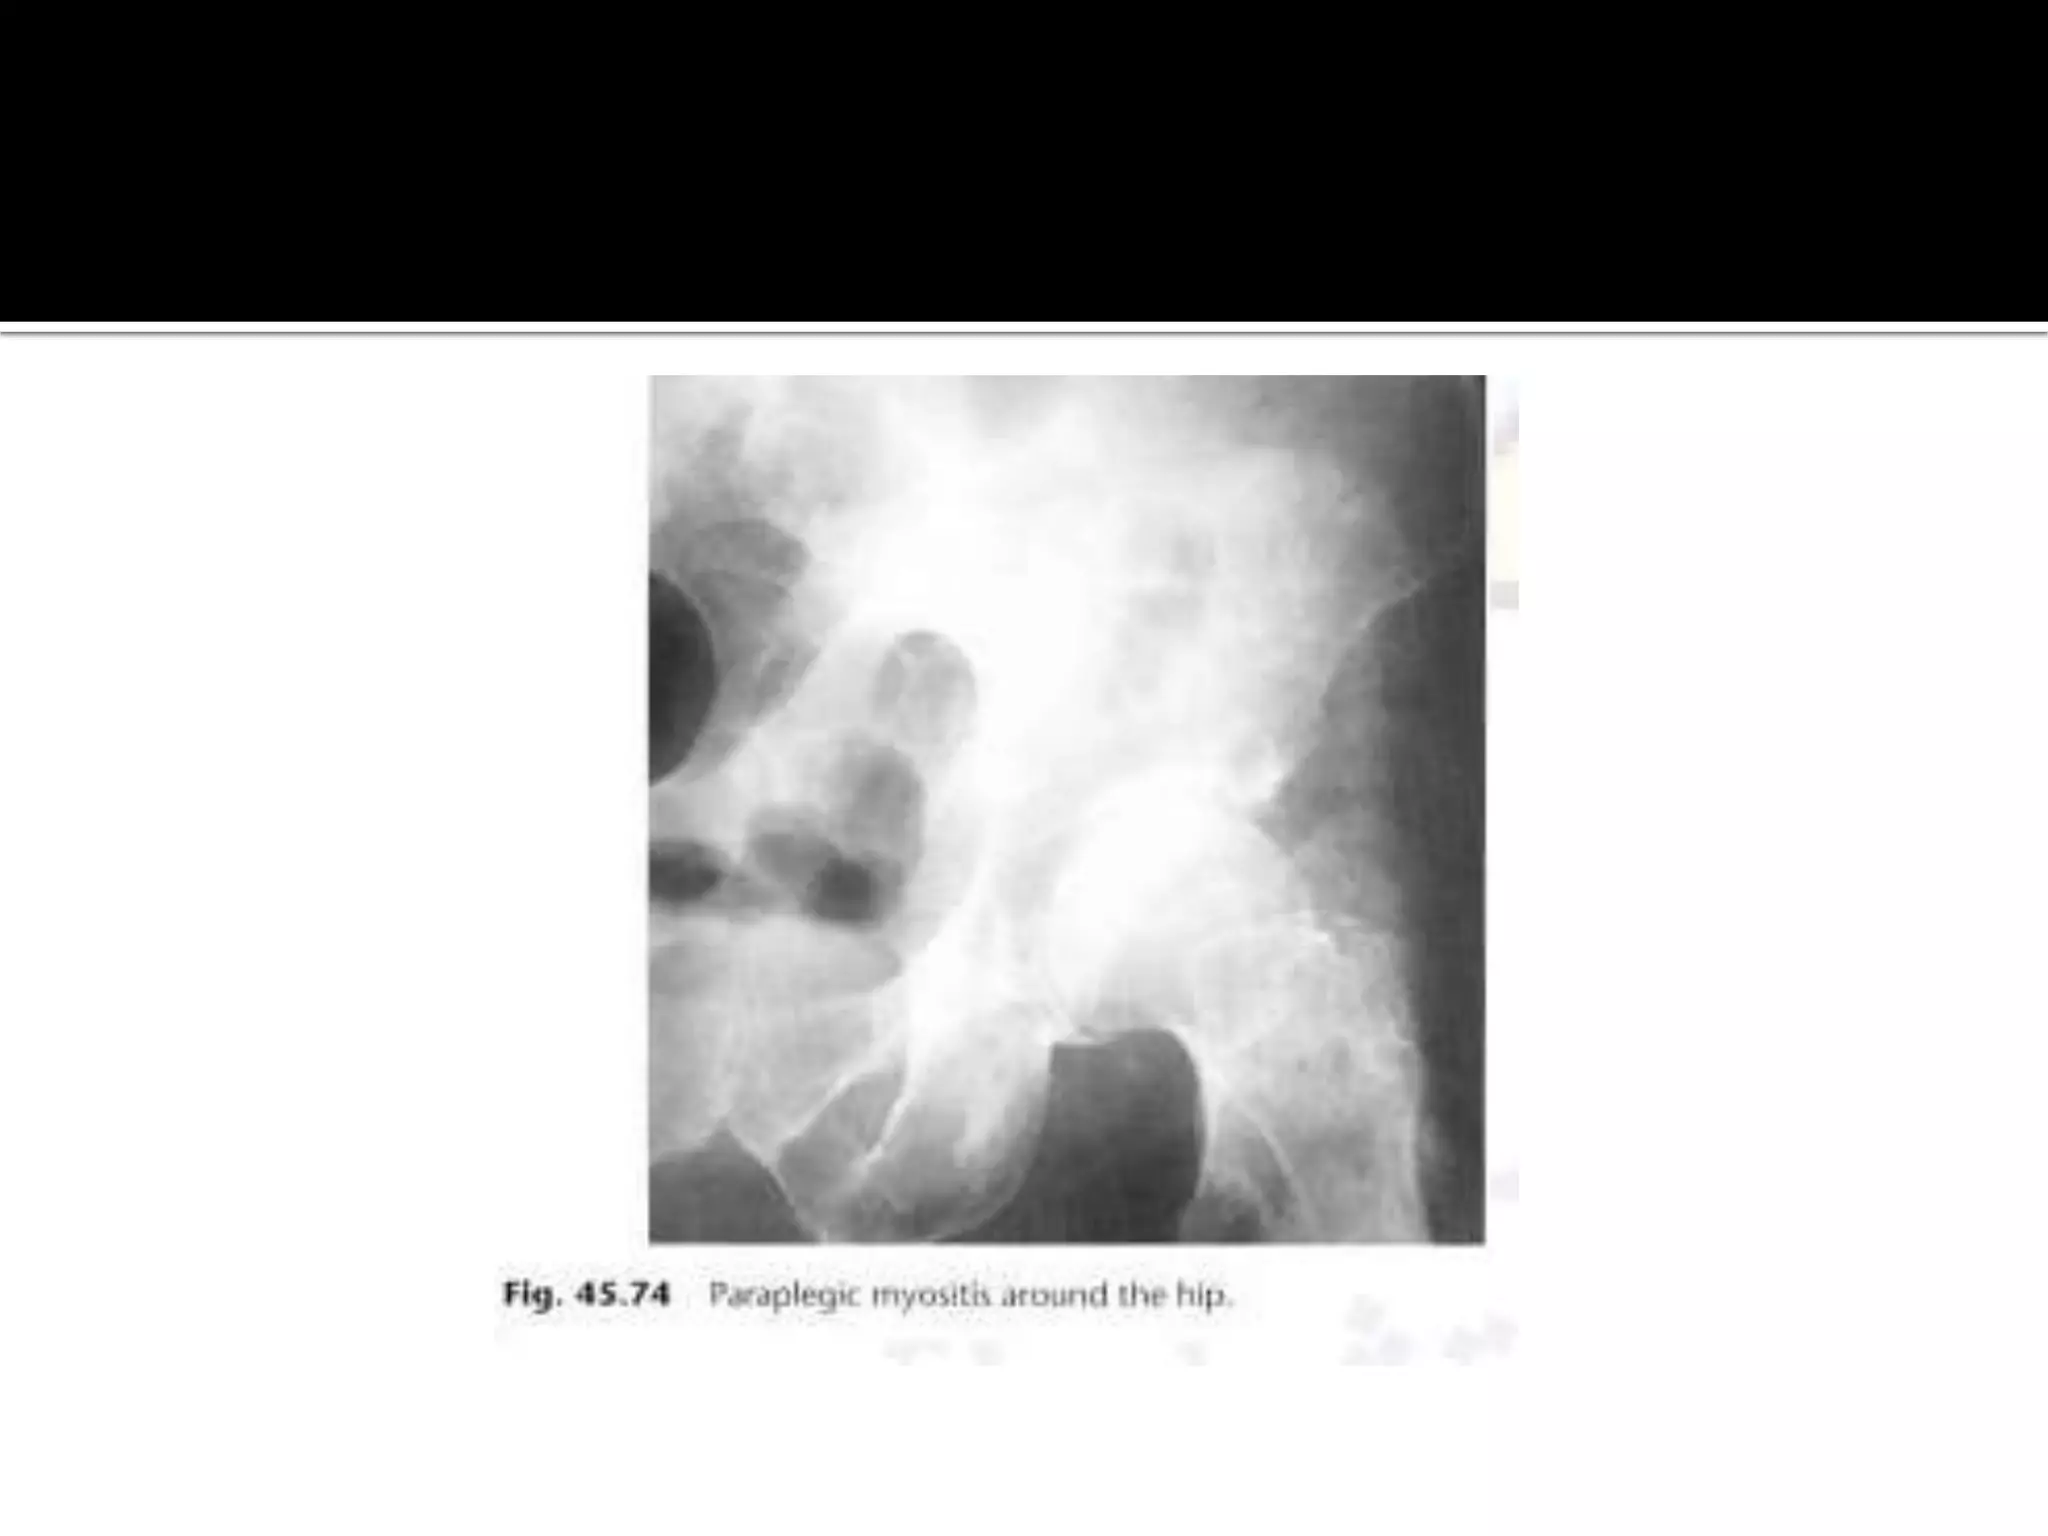

Paraplegic myocitis ossificans.

 it develops in paraplegics within 3-4 weeks below the

level of the paralysis.There is hetrotopic periarticular

calcification and ossification around the joints

particularly the hip with irregular plaques of bone

forming.

Post-traumatic myositis  itresults in a soft tissue mass which ossifies with a lacy pattern by 4-8 weeks.  common sites are the elbow and knee.The ossification may resolves. Paraplegic myocitis ossificans.  it develops in paraplegics within 3-4 weeks below the level of the paralysis.There is hetrotopic periarticular calcification and ossification around the joints particularly the hip with irregular plaques of bone forming.